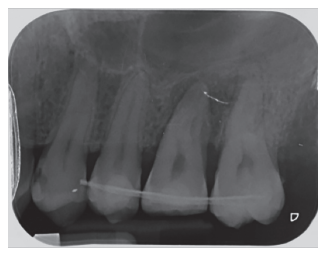

Tras rebajar la oclusión, se dio un punto en cruz con sutura monofilamento (Aragó®, Barcelona, España) alrededor del diente trasplantado para aumentar su fijación (Figura 13), realizándose una radiografía periapical intraoperatoria con técnica de paralelismo (Figura 14).